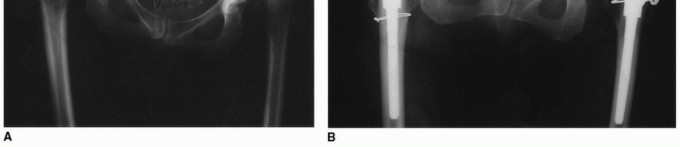

The epidemiology of conditions requiring modular femoral stems is diverse. Elements of developmental dysplasia of the hip (DDH) and structural deformity occur frequently in the primary THA population. A comprehensive review of 75 hips with a diagnosis of idiopathic osteoarthritis revealed proximal femoral deformity in 40% of hips and acetabular dysplasia in 39% of hips. The variable shape of the femoral canal, often quantified by the canal flare index, can lead to a significant proximal/distal mismatch. This mismatch makes it exceedingly difficult to achieve simultaneous proximal and distal fit and fill with a standard monolithic femoral component. If a monolithic stem is sized to fit a narrow distal canal, it may fail to adequately fill a capacious proximal metaphysis, leading to instability, subsidence, or inadequate stress transfer. Conversely, sizing a monolithic stem to fill a large proximal metaphysis may result in distal cortical impingement, intraoperative periprosthetic fracture, or thigh pain due to distal load transfer.

Other frequent conditions producing distorted anatomy include prior surgical interventions (such as proximal femoral osteotomies), posttraumatic deformities, and secondary osteoarthritis arising from childhood conditions like Legg-Calve-Perthes disease, slipped capital femoral epiphysis (SCFE), and prior hip sepsis. Less common conditions that frequently necessitate modularity include exceptionally small femoral canals seen in juvenile rheumatoid arthritis, dwarfism, and spondyloperipheral dysplasia. Conversely, pathologically large femoral canals, such as those classified as Dorr Type C bone, or those altered by ankylosing spondylitis, rheumatoid arthritis, alcoholic bone disease, and Paget disease, also represent primary indications for modular femoral reconstruction.

- Developmental Dysplasia of the Hip (DDH): Crowe Type III and IV DDH often present with excessive femoral anteversion, a narrow diaphysis, and a posteriorly displaced greater trochanter. Modular stems allow for distal fixation in the narrow canal and independent retroversion of the proximal body to correct the excessive native anteversion.

- Post-Traumatic Deformity: Malunions of intertrochanteric or subtrochanteric fractures often leave complex multi-planar deformities.

- Prior Osteotomy: Patients with a history of varus derotational osteotomies (VDRO) or valgus producing osteotomies present with distorted cervicodiaphyseal angles and retained hardware trajectories that dictate distal stem placement independent of proximal anatomy.